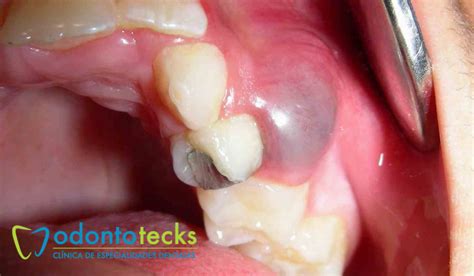

- Quistes dentígeros: Se forman alrededor de un diente que aún no ha erupcionado, debido a la acumulación de líquido entre la corona del diente y la capa externa del esmalte.

- Quistes dentígeros: Se procede a la extracción del diente afectado y un legrado de su encía para eliminar el quiste.